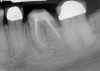

(1. ) Two-dimensional periapical radiograph of tooth No. 19 compared with a CBCT scan slice (0.1 mm) of the same tooth, which reveals a well-defined lesion that a patient can more easily understand.

Figure 1

(2.) Two-dimensional periapical radiograph of tooth No. 19 compared with a CBCT scan slice (0.1 mm) of the same tooth, which reveals a well-defined lesion that a patient can more easily understand.

Figure 2